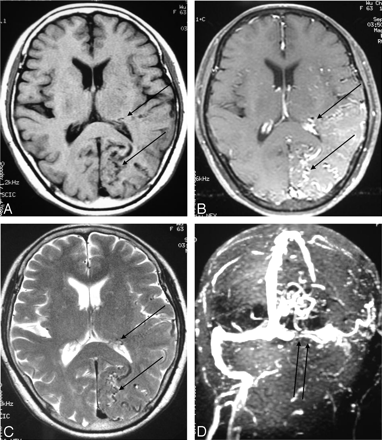

The imaging studies included noncontrast CT scan, 3D time-of-flight MR angiography (MRA) and MR imaging. CT demonstrated subcortical calcification, cerebral sulcus effacement, and a low attenuation area in the subcortical white matter on the left side (Fig 1). MR imaging (Fig 2) revealed multiple enhanced, punctate, and linear signal intensity voids, which indicates the presence of vessels over left cerebrum, and MRA showed multiple abnormal engorged vessels, which arose mainly from the external carotid artery. The left-side transverse sinus and sigmoid sinus were not identified on MR venography (Fig 2D). Digital subtraction angiography (DSA) revealed an AVF of the left transverse and sigmoid sinus (Fig 3) with main feeding vessels from both external carotid arteries. The main venous drainage was through the right transverse and sigmoid sinus, but there was retrograde flow into the straight sinus and superior sagittal sinus, which caused diffuse engorgement of the superifical cortical and the deep intramedullary veins. Occlusion of left transverse and sigmoid sinus was noted. Because of the retrograde flowing pattern of the dural sinus AVF and refluxing into cortical veins, the final diagnosis was type II a + b dural AVF.

Axial section of brain.

A and B, Pre- and postgadolinium enhancing T1-weighted image (TR/TE/NEX/Matrix, 500/19/2/256 × 256).

C, T2-weighted image (3,200/106/1/256 × 256).

D, MR venography (TR/TE/flip angle, 26/5/20). Multiple tortuous, enhanced cortical and intramedullary vessels (single arrows) were noted over left temporal and occipital region with left transverse sinus occlusion (double arrows).